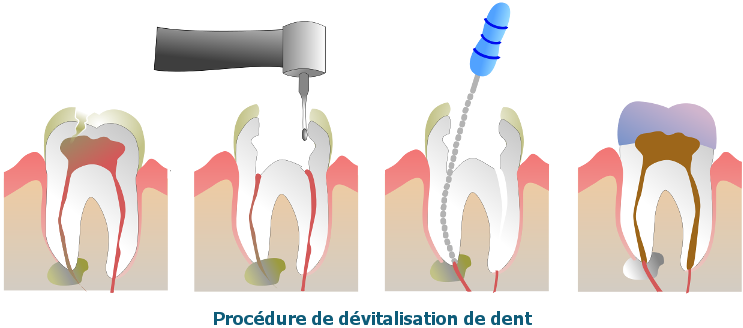

La dévitalisation, aussi appelée traitement endodontique, permet de conserver votre dent naturelle. Elle consiste à retirer la pulpe dentaire, nettoyer et désinfecter les canaux, puis les obturer avec un matériau étanche.

Ce traitement est indiqué dans les cas suivants :

Cependant, la dent dévitalisée devient plus fragile, nécessite souvent la pose d'une couronne, et peut demander plusieurs séances de traitement.

Le traitement endodontique se déroule sous anesthésie locale. Le praticien retire la pulpe infectée, nettoie les canaux radiculaires, puis les scelle à l'aide d'un matériau biocompatible.